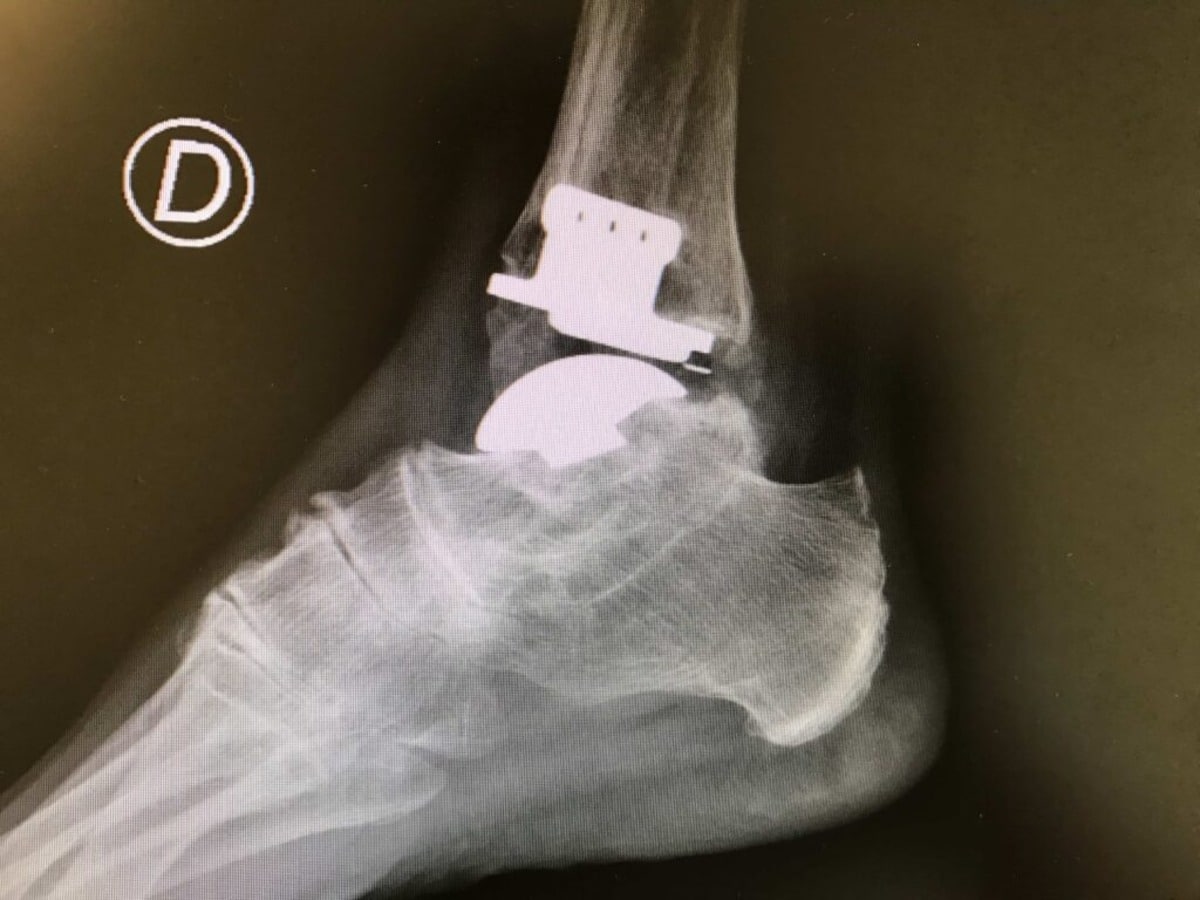

L’opération dure environ 1h30 à 2h. Elle peut se faire en chirurgie ouverte (avec une incision visible) ou de façon mini-invasive par arthroscopie, selon le contexte.

- Fixation solide avec vis, plaques, ou clou centromédullaire,